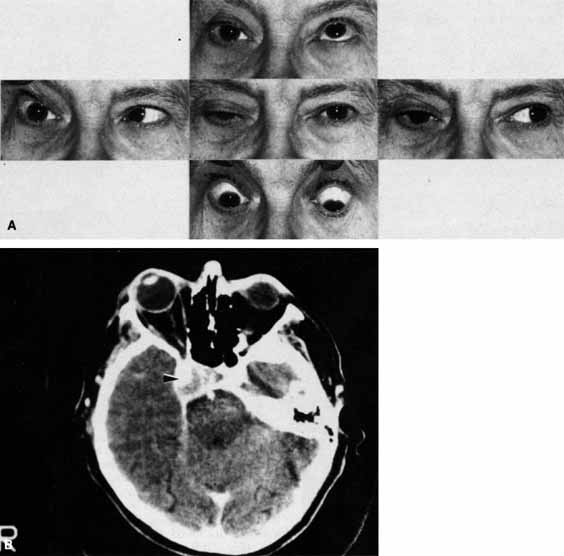

A 70-year-old woman presented with a 6-month history of progressive diplopia and ptosis. She demonstrated complete right third, fourth, and sixth cranial nerve palsies, and hypesthesia of cranial nerve V1 (Fig. 22A). The right pupil was dilated. Computed tomography (CT) disclosed an intracavernous aneurysm (see Fig. 22B).

Fig. 22 A. A 70-year-old woman with complete right third, fourth, and sixth cranial nerve palsies. Hypesthesia of cranial nerve V1 was also present. B. CT scan demonstrates an intracavernous aneurysm (arrow).

The so-called superior orbital fissure syndrome occurs when an infiltrative, inflammatory, or ischemic event occurs within the superior orbital fissure, but not in the orbital apex.4 A complete superior orbital fissure syndrome occurs when all the neurovascular components passing through the superior orbital fissure are damaged, producing a total ophthalmoplegia, ptosis, and anesthesia of cranial nerve V1 (see Fig. 22A). The pupil may be dilated, miotic, or midposition and fixed, depending on the balance of parasympathetic and sympathetic damage. The superior ophthalmic vein, best seen on CT, may be dilated if venous outflow from the orbit is obstructed. Clues to venous outflow obstruction are increased intraocular pressure, fullness of the upper eyelid, and hyperemia of the deep Tenon's vessels. Ophthalmoscopically, the retinal veins may be dilated. The effect of a lesion in the superior orbital fissure or the anterior cavernous sinus cannot be differentiated clinically (see Fig. 22B). When the posterior cavernous sinus becomes involved, hypesthesia of cranial nerve V2 may also be present.

The only difference between a superior orbital fissure syndrome and an orbital apex syndrome is the presence of visual loss caused by optic nerve involvement. Visual acuity, color vision, or the visual field are abnormal. An ipsilateral relative afferent pupil defect is present.

A 30-year-old man noted diplopia and right ptosis for the past month. The patient demonstrated normal vision and symmetric pupils but had a neurogenic ptosis (Fig. 23A) and limited right supraduction (Fig. 23B). Otherwise his extraocular movements were full. CT demonstrated an intracranial aneurysm of the posterior communicating artery aneurysm (Fig. 23C).

Fig. 23 A. A 30-year-old man demonstrates a neurogenic right ptosis. The pupils are symmetric. B. Supraduction of the right eye is limited. Paresis of the superior branch of cranial nerve III was diagnosed. C. Computed tomography (CT) demonstrates a posterior communicating artery aneurysm (arrow).

Anatomically, the third cranial nerve branches into its superior and inferior divisions as it enters the orbit through the superior orbital fissure. Superior branch damage results in ptosis (levator muscle) and decreased supraduction (superior rectus muscle). Inferior branch damage results in decreased adduction (medial rectus), decreased infraduction (inferior rectus), decreased excycloduction (inferior oblique), and a dilated pupil (parasympathetic). Anatomically, a cranial nerve III branch nerve lesion seems to imply an anterior cavernous sinus or orbital apex localization. However, functionally, the third cranial nerve may bifurcate in the intracranial portion of the nerve, so cranial nerve III branch nerve palsies have been demonstrated with intracranial lesions. The localizing finding of a cranial nerve III branch nerve lesion is therefore not absolute (see Fig. 23).46